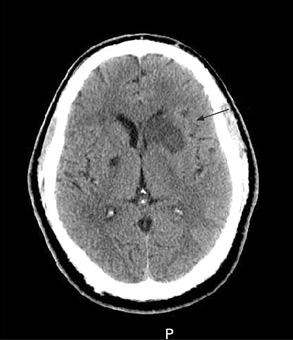

- TC de la cabeza sin contraste

- IRM de la cabeza